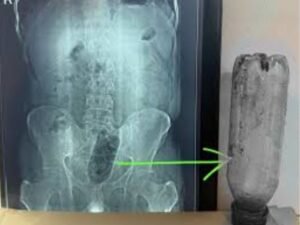

यहां डॉक्टरों ने युवक का एक्स-रे कराया तो मल द्वार के पास एक बोतल फंसी हुई दिखाई दी। डॉक्टरों ने युवक को एडमिट करके इलाज शुरू किया। करीब 1 घंटे के ऑपरेशन के बाद युवक को डिस्चार्ज कर दिया गया। डॉक्टरों का कहना है कि-युवक साइको सेक्सुअल डिसआर्डर एनल एयरोटिसिस्म से पीड़ित है।

शाहगंज क्षेत्र में रहने वाला 38 साल का एक युवक साकेत कॉलोनी के नवदीप हॉस्पिटल पहुंचा था। वह दर्द से कराह रहा था। डॉक्टर ने एक्सरे में देखा कि मलाशय में 1 लीटर पानी की प्लास्टिक बोतल फंसी हुई थी। उसके मलाशय में घाव थे। जिस वजह से वह शौच करने नहीं जा रहा था। असहनीय दर्द होने के कारण वह हॉस्पिटल आया था।